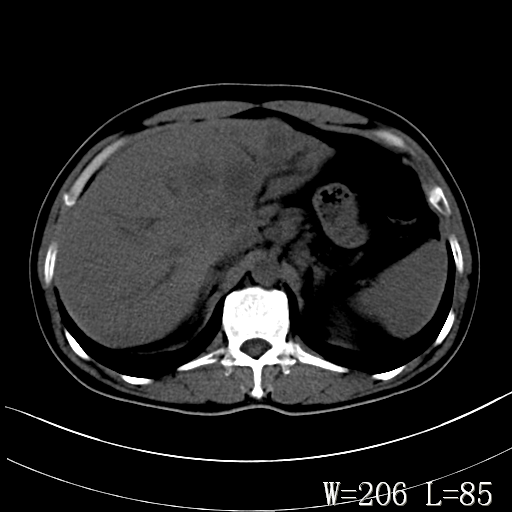

标题: CT27340:肝脏病变? [打印本页]

标题: CT27340:肝脏病变?

男,45岁,发热、乏力半月,午后为主。

对比剂快进快出,首先考虑肝左叶巨块型肝癌。

其次,感染性病变,如肝脓疡不排除。

蜂巢,肝脓肿

蜂巢状,支持!肝脓肿的诊断。

考虑肝内胆管细胞癌。